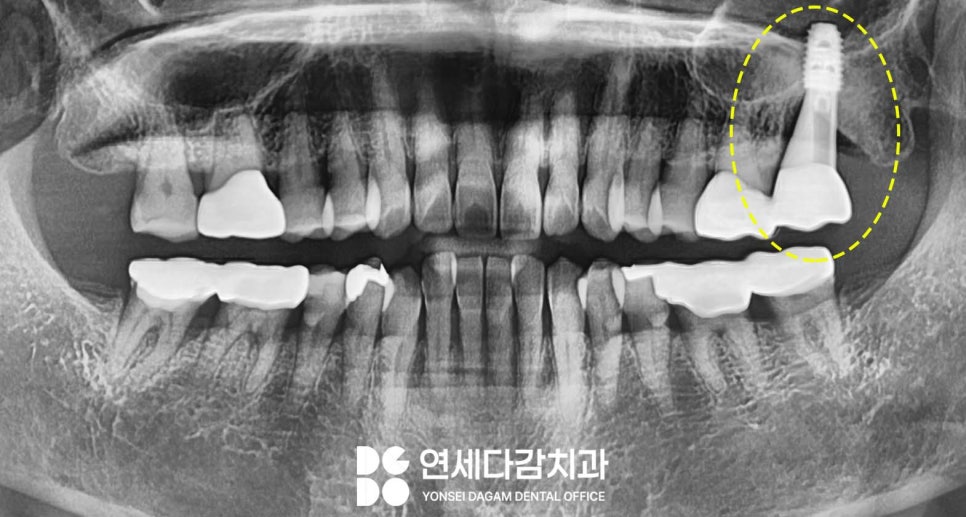

정밀 검사를 통해 환자 기준 왼쪽 위

어금니 주변을 살펴본 결과,

치아 뿌리 주변으로 심한 염증이

발생하여 치조골(치아를 지지하는 뼈)이

흡수된 상태였습니다.

이러한 상태는 이가 흔들리는

주된 원인이었습니다.

그뿐만 아니라

그 치아의 치근단(뿌리 끝) 부위 주변으로

비정상적으로 위치한

매복 사랑니가 있다는 것이었습니다.

송파역 치과 에서 분석해 봤을 때

어금니의 병소가 커지면서,

주변 구조에 변화를 일으켜

발육 위치가 변이된 것으로 판단됩니다.